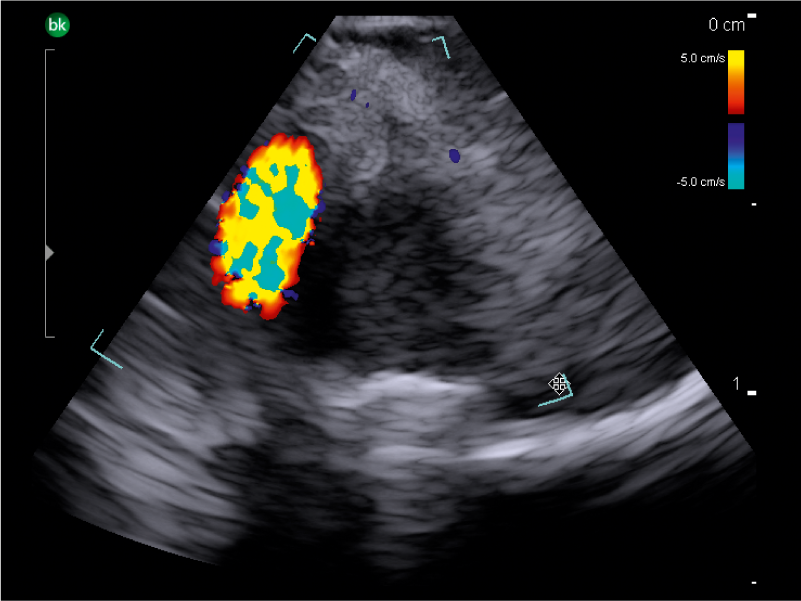

REAL-TIME VISUALIZATION HAS NEVER LOOKED THIS GOOD

- Enhanced Visualization: Improved algorithms for greater details around lesion borders, and automated high-resolution image settings.